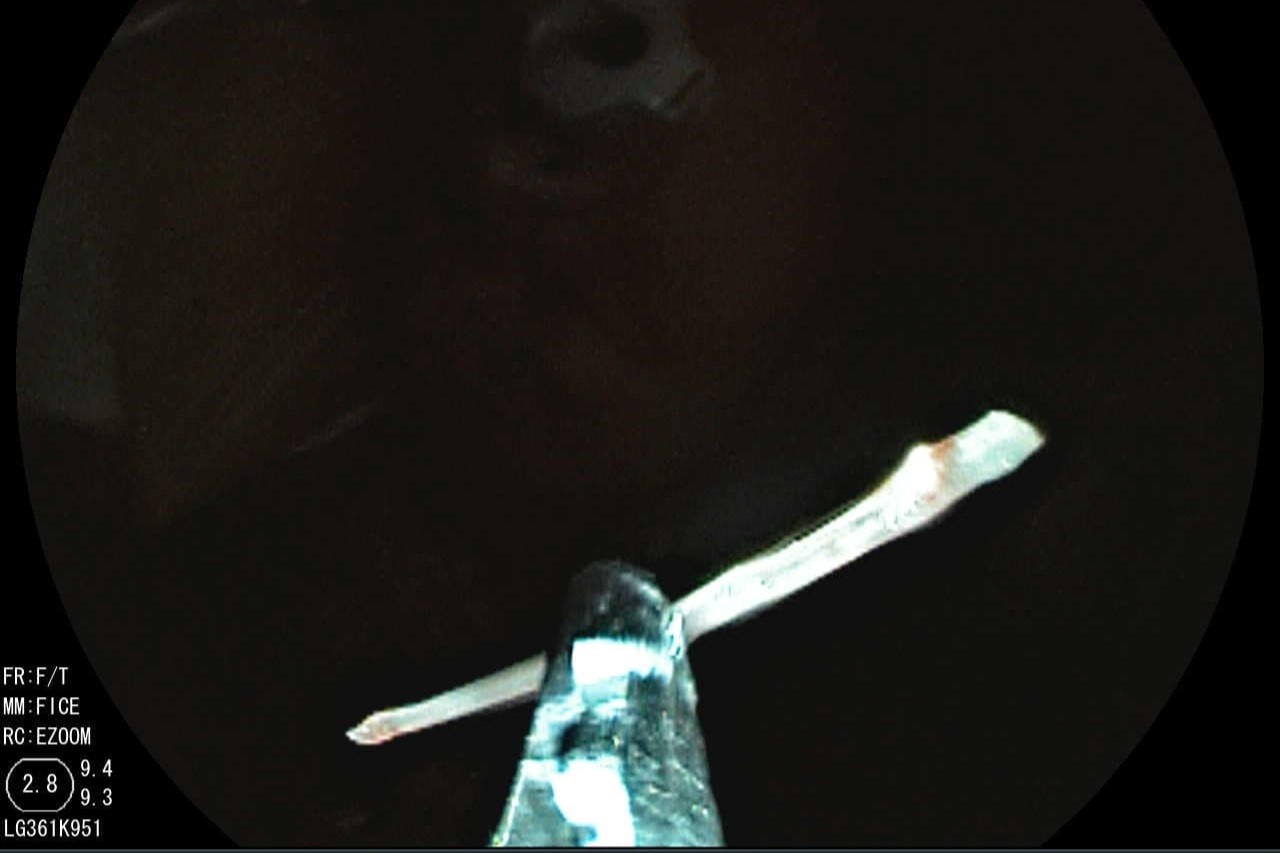

Hình ảnh nội soi mảnh xương trong họng của người đàn ông. Ảnh: BVCC.

Hình ảnh nội soi cho thấy có mảnh xương cá găm sâu vào gốc lưỡi, niêm mạc xung quanh phù nề. Sau 15 phút, các bác sĩ đã gắp được mảnh xương cá qua nội soi bằng dụng cụ chuyên dụng, không gây chảy máu. Mảnh xương dài xấp xỉ 2,5 cm, có một đầu nhọn. Bệnh nhân sau đó cũng trở lại hoạt động bình thường.